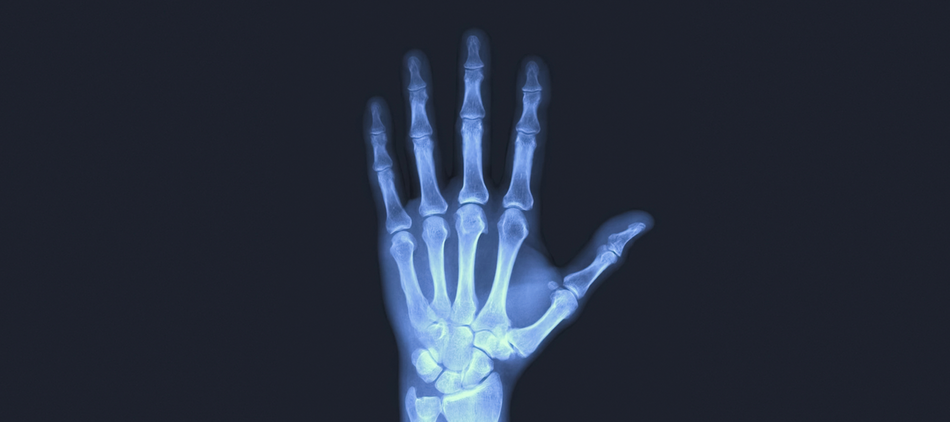

повернутися до статті Міняйте фотографії за допомогою стрілок на клавіатурі 3 / 4 Przełomowy wynalazek naukowców z Uniwersytetu Łódzkiego. Biokompozyty do regeneracji kości Przełomowy wynalazek naukowców z Uniwersytetu Łódzkiego. Biokompozyty do regeneracji kości / fot. Bartosz Kałużny ДИВІТЬСЯ ТАКОЖ Naukowcy z Uniwersytetu Łódzkiego w Peru. Stoją na straży szczątek i dziedzictwa kulturowego Startup z Łodzi stworzył...karmiącego robota! Rozwiązanie wspiera osoby z niepełnosprawnościami! Wakacyjne remonty szkół w Łodzi na półmetku. Sprawdź, gdzie trwają prace [ZDJĘCIA]